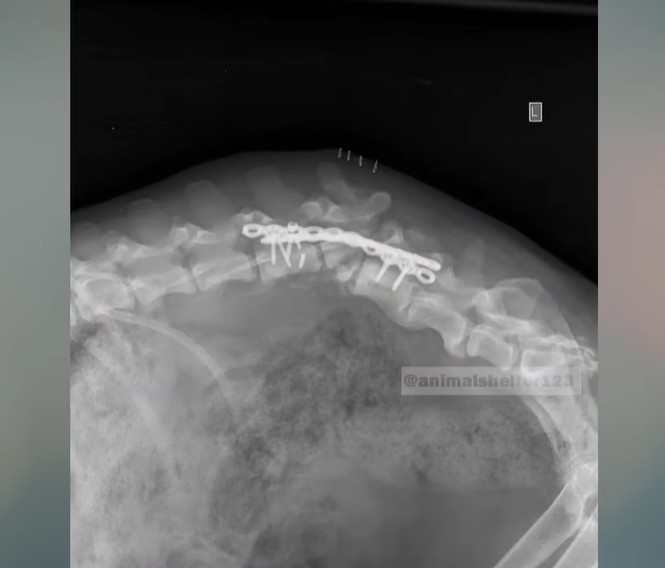

The medical examinations, however, brought incredibly heavy news. Indra’s spine was literally snapped in half. The veterinary team was stunned; it was the most severe spinal trauma they had ever encountered in their careers. She would need two complex surgeries just to manage the pain and align her back, but the paralysis from the waist down was entirely permanent.